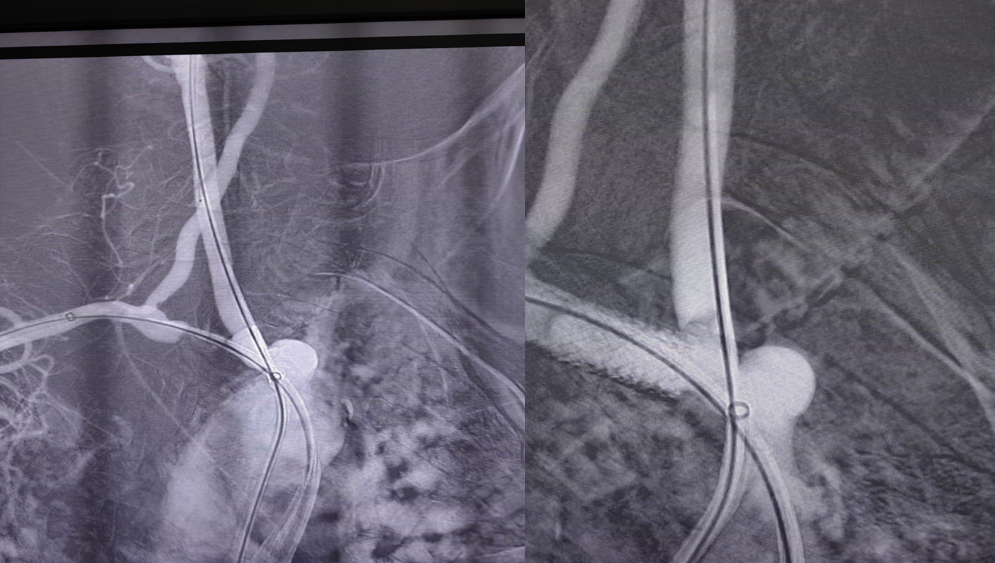

图:术中CTA图像指导导丝导管方向

02

病例二

复杂的右锁骨下动脉闭塞病变:

对于闭塞病变,开通导丝的方向至关重要。根据CTA提示的特定角度(如 RAO 32° CRA 12°)进行投照,能为术者提供最清晰的路径导向,成功引导导丝通过闭塞段。

图:CTA提示 RAO 32  CRA 12

图:按RAO 32  CRA 12开通成功